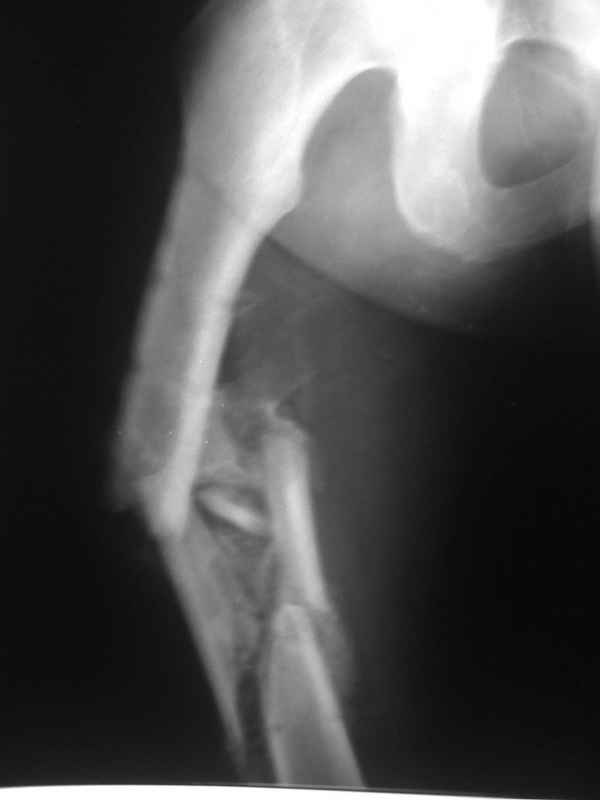

Re: Неправильно срастающийся оскольчатый перелом бедра

Конечно, снимки для планирования надо нормальные, не такой огрызок.

Можно закрыто мобилизовать отломки, наложить дистракционный аппарат, восстановить ось и длину, да и заштифтовать, на всякий случай с антибиотиковым цементным покрытием.

Спасибо за снимки. Предложения по тактике прежние.